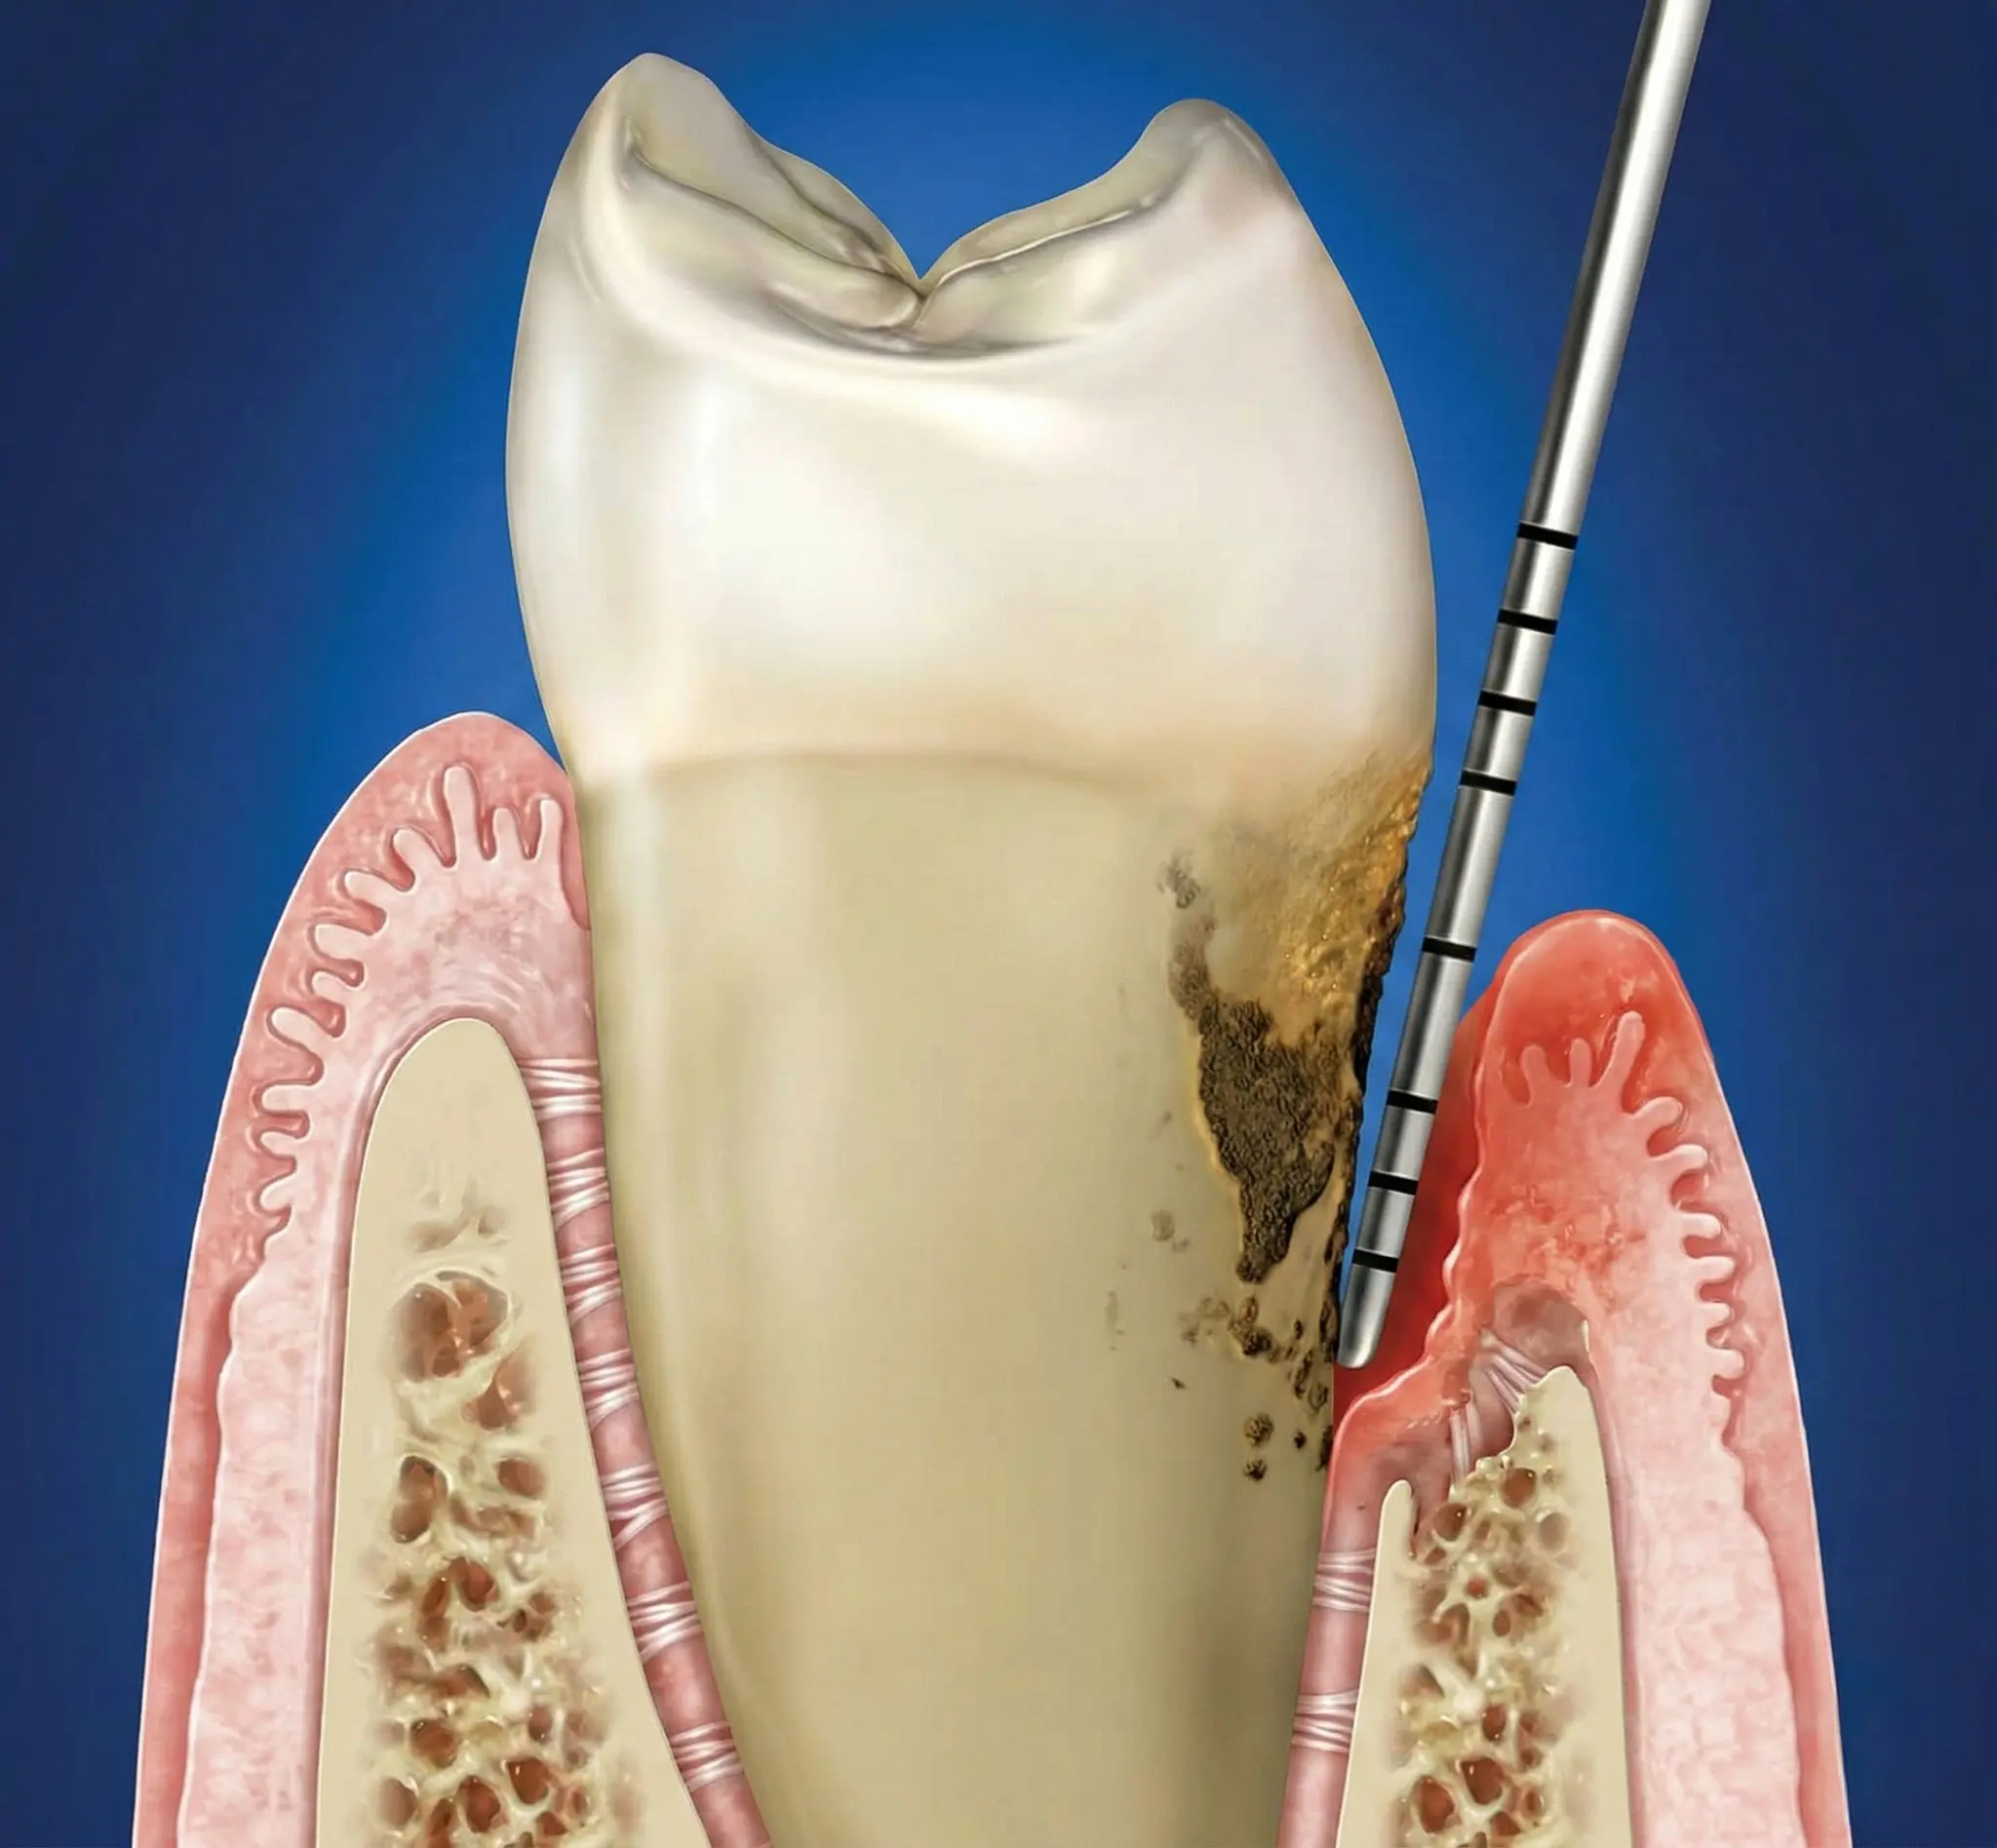

Bone-level, tissue-level, connessione conica: la profondità corretta cambia con il tipo di connessione. Perché sbagliarla causa riassorbimento osseo.

Un impianto mal posizionato causa perdita ossea di 0,25 mm ogni 10° di errore. Come riconoscere il problema, quando si può correggere e quando va rimosso.

Negli ultimi decenni si è enfatizzato il rischio di peri-implantite negli impianti a superficie ruvida, ma non tutti ne sono affetti. Problemi come erra...